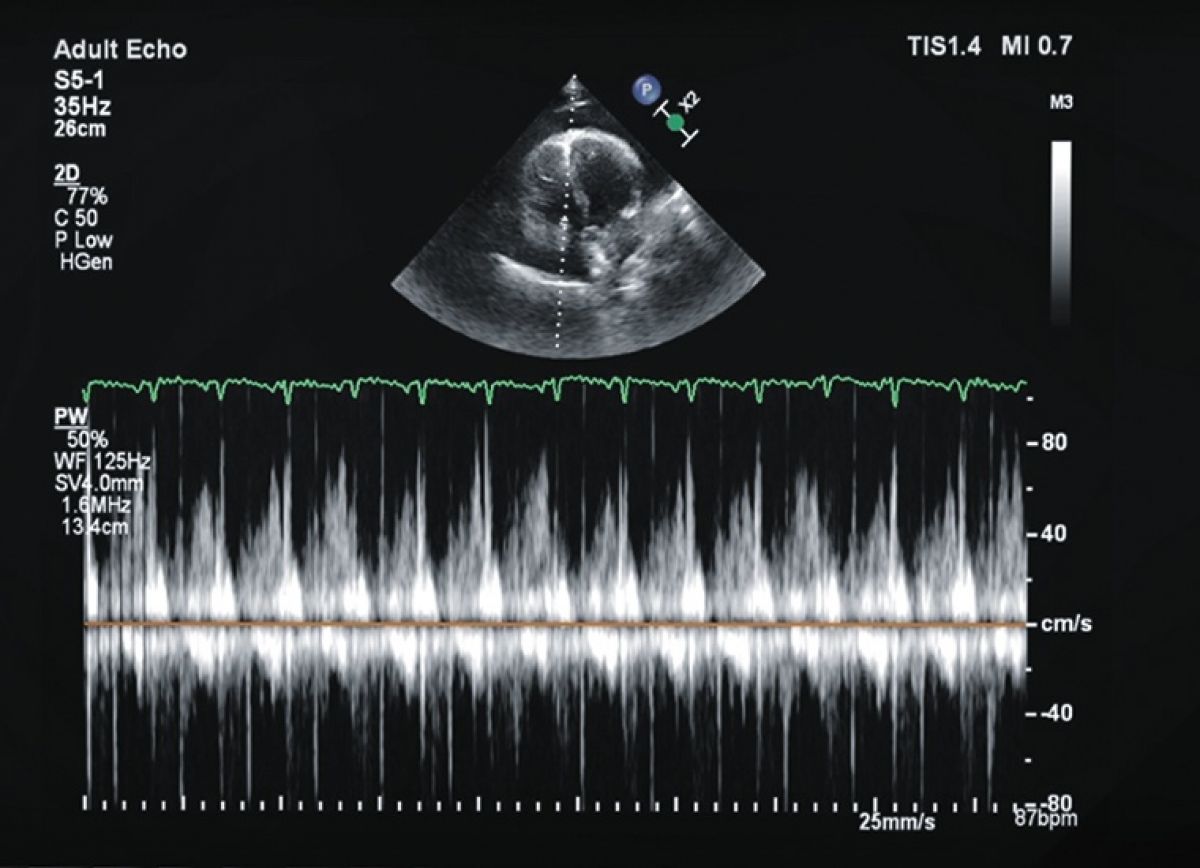

Pacjentka dusznością wysiłkową; w wywiadzie leczenie operacyjne z powodu raka pęcherza moczowego

Płyn w worku osierdziowym

Ocena płynu w worku osierdziowym i cech tamponady